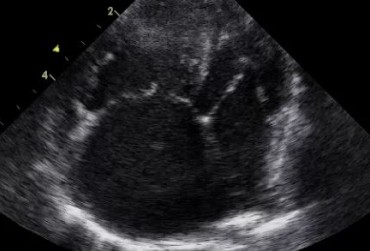

Dysplazja zastawki trójdzielnej i zespół Wolffa–Parkinsona–White’a u kota – opis przypadku

Zwężenie zastawki trójdzielnej jest jedną z form dysplazji pojawiającą się w różnym stopniu nasilenia (najczęściej łącznie z niedomykalnością zastawki) zarówno u psów, jak i u kotów. Cechami charakterystycznymi definiującymi zwężenie zastawki trójdzielnej są: obecność rozkurczowego wybrzuszenia (doming) płatków zastawki, zmniejszona ruchomość płatków, zmniejszona średnica ujścia zastawki. Mimo że zmiany morfologiczne aparatu trójdzielnego są typowe w przebiegu TVD i są znakiem rozpoznawczym tej choroby, nie są one zawsze bardzo silnie wyrażone i nie zawsze można mieć bezsprzeczną pewność diagnostyczną, bazując na badaniu echokardiograficznym [10]. Przypadki takie zdarzają się przede wszystkim u pacjentów, u których nie postawiono diagnozy we wczesnym etapie życia, a którzy pojawiają się na badaniu dopiero w starszym wieku z zaawansowanymi zmianami i niejednokrotnie z klinicznymi objawami prawostronnej niewydolności mięśnia sercowego i towarzyszącymi zaburzeniami w rytmie. W takich przypadkach obraz choroby może przypominać arytmogenną kardiomiopatię prawokomorową (arrhythmogenic right ventricular cardiomyopathy – ARVC) [1, 8]. Preekscytacja jest często obserwowana u ludzi z anomalią Ebsteina. U zwierzat, podobnie jak u ludzi, obecność dodatkowej drogi przewodzenia może nigdy nie prowadzić do rozwoju tachykardii nadkomorowej lub arytmia ta pojawiać się może dopiero w późniejszym okresie życia. Opisany przypadek jest przykładem pacjenta z dysplazją zastawki trójdzielnej i prawostronną niewydolnością serca będącą najprawdopodobniej konsekwencją tachykardii nadkomorowej.